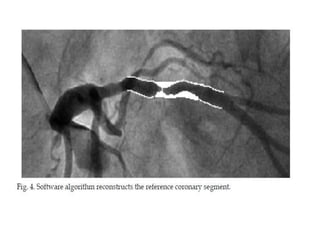

Quantitative Coronary Angiogram

• 2 Dimensional & 3 Dimensional.

• Earlier manually done by calipers later done through

computers.

• Invented by Greg Brown in University of Washington

30 yrs back

• Good quality angiograms at least two orthogonal views

required to avoid

foreshortening, vessel overlapping, irregular margins.

3 D imaging utilizes standard 2 D images 30` apart and

reconstructs

Quantitative Coronary Angiogram •2 Dimensional & 3 Dimensional. • Earlier manually done by calipers later done through computers. • Invented by Greg Brown in University of Washington 30 yrs back • Good quality angiograms at least two orthogonal views required to avoid foreshortening, vessel overlapping, irregular margins. 3 D imaging utilizes standard 2 D images 30` apart and reconstructs